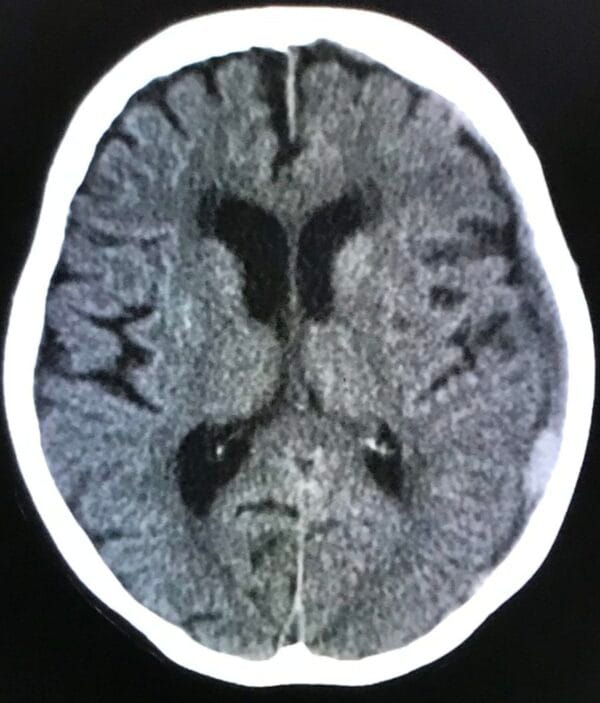

次に、8月下旬、同医師から時々意識・記憶が薄くなりボーッとしていることがあり心配なので、救急外来に行って詳しい検査を受けて欲しいとの連絡。

8月27日に大雨の中、検査を受けに行き、翌日28日に、慢性硬膜下血腫の疑いがあると診断。

特に治療は行わず、1カ月程度後に再度検査を行うということで、再診予約。

9月25日に再度検査をした結果、血腫は消えており、一過性のものだったと。一件落着。

※8月27日撮影画像

※9月25日再撮影画像:上の画像の右周縁部にある陰が消えている